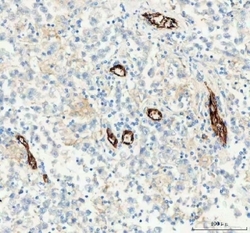

Supportive validation

- Submitted by

- NSJ Bioreagents (provider)

- Main image

- Experimental details

- IHC-P: CD31 antibody testing of human intestinal cancer tissue

- Submitted by

- NSJ Bioreagents (provider)

- Main image

- Experimental details

- IHC staining of FFPE human liver cancer tissue with CD31 antibody. HIER: boil tissue sections in pH8 EDTA for 20 min and allow to cool before testing.

- Submitted by

- NSJ Bioreagents (provider)

- Main image

- Experimental details

- IHC staining of FFPE human glioblastoma tissue with CD31 antibody. HIER: boil tissue sections in pH8 EDTA for 20 min and allow to cool before testing.